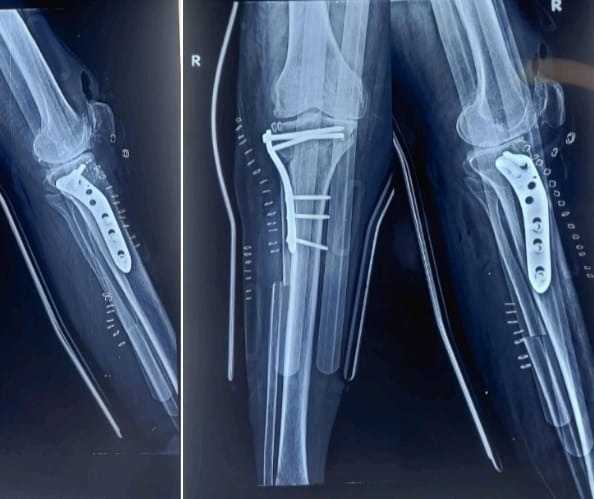

लखनऊ। उत्तर प्रदेश में पहली बार, संजय गांधी पीजीआई लखनऊ के आर्थोपेडिक विभाग ने एक अत्याधुनिक संयुक्त घुटना सर्जरी को सफलतापूर्वक अंजाम दिया है। इस अभिनव प्रक्रिया में आर्थ्रोस्कोपिक माइक्रोफ्रैक्चर और हाइब्रिड हाई टिबियल ऑस्टियोटॉमी (HTO) को एक ही ऑपरेशन में किया गया। यह सर्जरी 46 वर्षीय महिला मरीज पर की गई, जो गंभीर ऑस्टियोआर्थराइटिस और अधिक वेरस विकृति से वर्षों से पीड़ित थीं।

दूसरा और अधिक जटिल चरण था हाइब्रिड हाई टिबियल ऑस्टियोटॉमी (HTO)। इसमें टिबिया (पिंडली की हड्डी) को सटीक रूप से काटकर पुनः संरेखित किया गया, ताकि वजन का भार घुटने के क्षतिग्रस्त आंतरिक हिस्से से हटकर स्वस्थ बाहरी हिस्से पर शिफ्ट हो सके। इस सुधार से वेरस विकृति ठीक होती है और घुटने के प्राकृतिक जोड़ की आयु में उल्लेखनीय वृद्धि होती है।